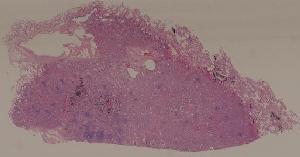

49.梅毒性主动脉炎

50.大叶性肺炎

51.肺肉质变

52.小叶性肺炎

57.肺癌

59.慢性萎缩性胃炎

60.胃溃疡

61.胃腺癌(胃粘液腺癌)

62.急性普通型病毒性肝炎

63.慢性活动性肝炎

64.急性重型病毒性肝炎

65.亚急性重型病毒性肝炎

66.活动性结节性肝硬化

67.非活动性结节性肝硬化

68.胆汁性肝硬化

69.肝细胞性肝癌

72.膜性肾小球肾炎

73.急性肾小球肾炎

74.新月体性肾炎

75.慢性硬化性肾小球肾炎